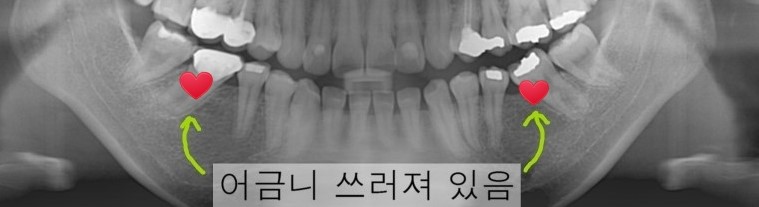

이번에 내원하신 환자분은

돌출입도 있지만

충치로 빠진 어금니 자리로

뒤쪽 어금니가

심하게 누어 있는 상황 입니다.

엑스레이 상으로는

살짝 기대어 있는 것처럼

보이지만,

실제는

많이 누어 빠진 공간의

틈을 완벽하게 채운 상태입니다.

이정도면 치아가 빠진지

2년이상 된 경우라 볼수 있습니다.

치아가 빠지고 나면

주변에 있는 치아들이

이렇게 쓰러지면서

공간을 막기 때문에

어금니 교합이 좋지 않고

잇몸도 시간이 갈수록

나뻐지게 됩니다.